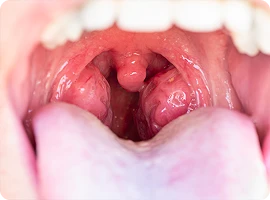

Viêm họng, viêm amidan mãn tính

Viêm amidan mãn tính